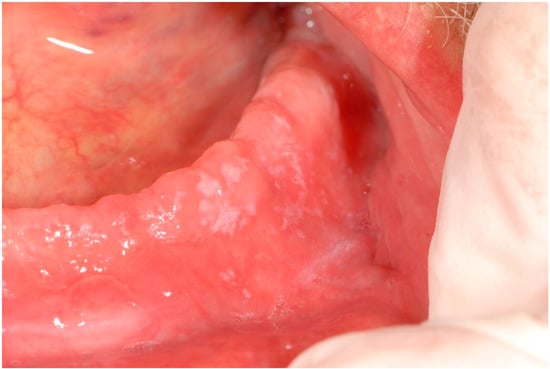

| 4 | Removable whitish plates Erythematous area Xerostomia | Candidiasis (pseudomembranous candidiasis, median rhomboid glossitis) | Dorsal tongue Oral mucous membranes | Nystatin Mucosamin® mouthwash | 3rd dose 9th dose |

| 6 | Non-removable whitish lesions | Hyperkeratosis | Palate Cheek mucosa | Aminogam® mouthwash | 4th dose |

| 7 | Non-removable white lesions | Hyperkeratosis | Dorsal tongue Palate | Aminogam® mouthwash | 3rd dose |

| 12 | Non-removable whitish lesions | Epithelial atrophy and hyperkeratosis without dysplasia | Cheek Dorsal tongue | Aminogam® mouthwash | 4th dose |

| 13 | Erythematous area Ulcer Removable whitish plates | Epithelial atrophy without dysplasia Ulcer Candidiasis | Palate Tuberosity Dorsal tongue Alveolar process | Nystatin | 2nd dose 4th dose |